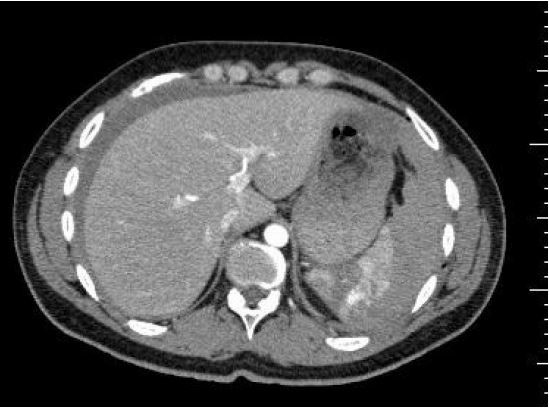

Homem 21a, vítima de agressão interpessoal é encaminhado para Unidade de Emergência Referenciada de um hospital terciário devido dor em hipocôndrio esquerdo para avaliação da equipe cirúrgica. Apresenta-se consciente e orientado; PA= 102x72mmHg; FC= 103bpm; FR= 18irpm; oximetria de pulso (ar ambiente): 99%. Realizou Tomografia Computadorizada com o seguinte achado:

Mediante o quadro clínico e exame complementar, a conduta é: